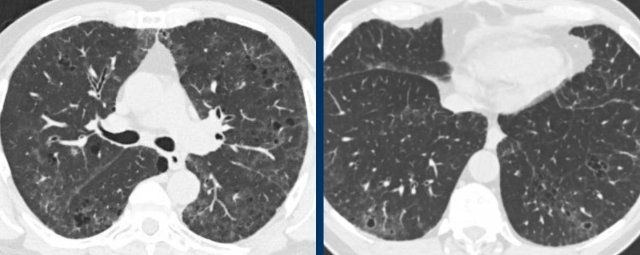

These are images of two different patients.

Study the image.

What is the most characteristic finding?

What is the most likely diagnosis?

Findings

Although at first glance these images look similar, you may notice that on the left we have true cysts with a wall in a patient with advanced LCH, while on the right some appear to have a wall, but most of them do not.

This is centrilobular emphysema.